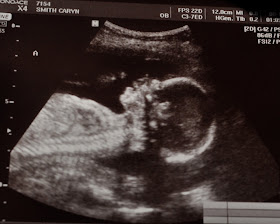

Baby B waving:

Baby A:

Baby A had a slightly enlarged kidney which they will keep an eye on but are confident that it should take care of itself.